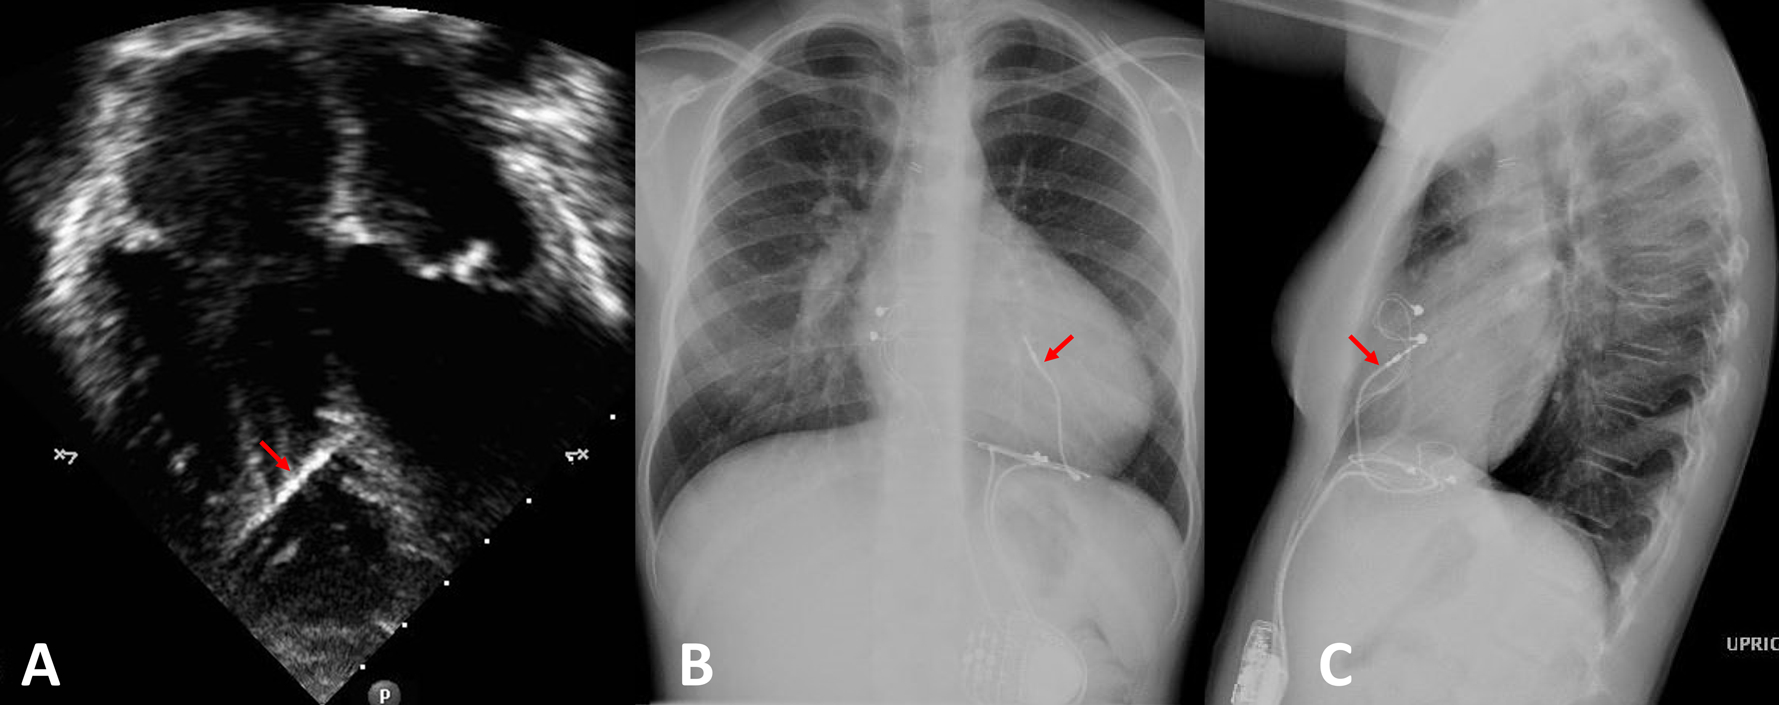

Figure 1:

The position of the RV endocardial lead affixed to the interventricular septum is demonstrated in an echocardiographic apical 4 chamber view (panel A) and chest X-ray (posterior-anterior view in panel B, lateral view in panel C). The RV septal lead is indicated with a red arrow.